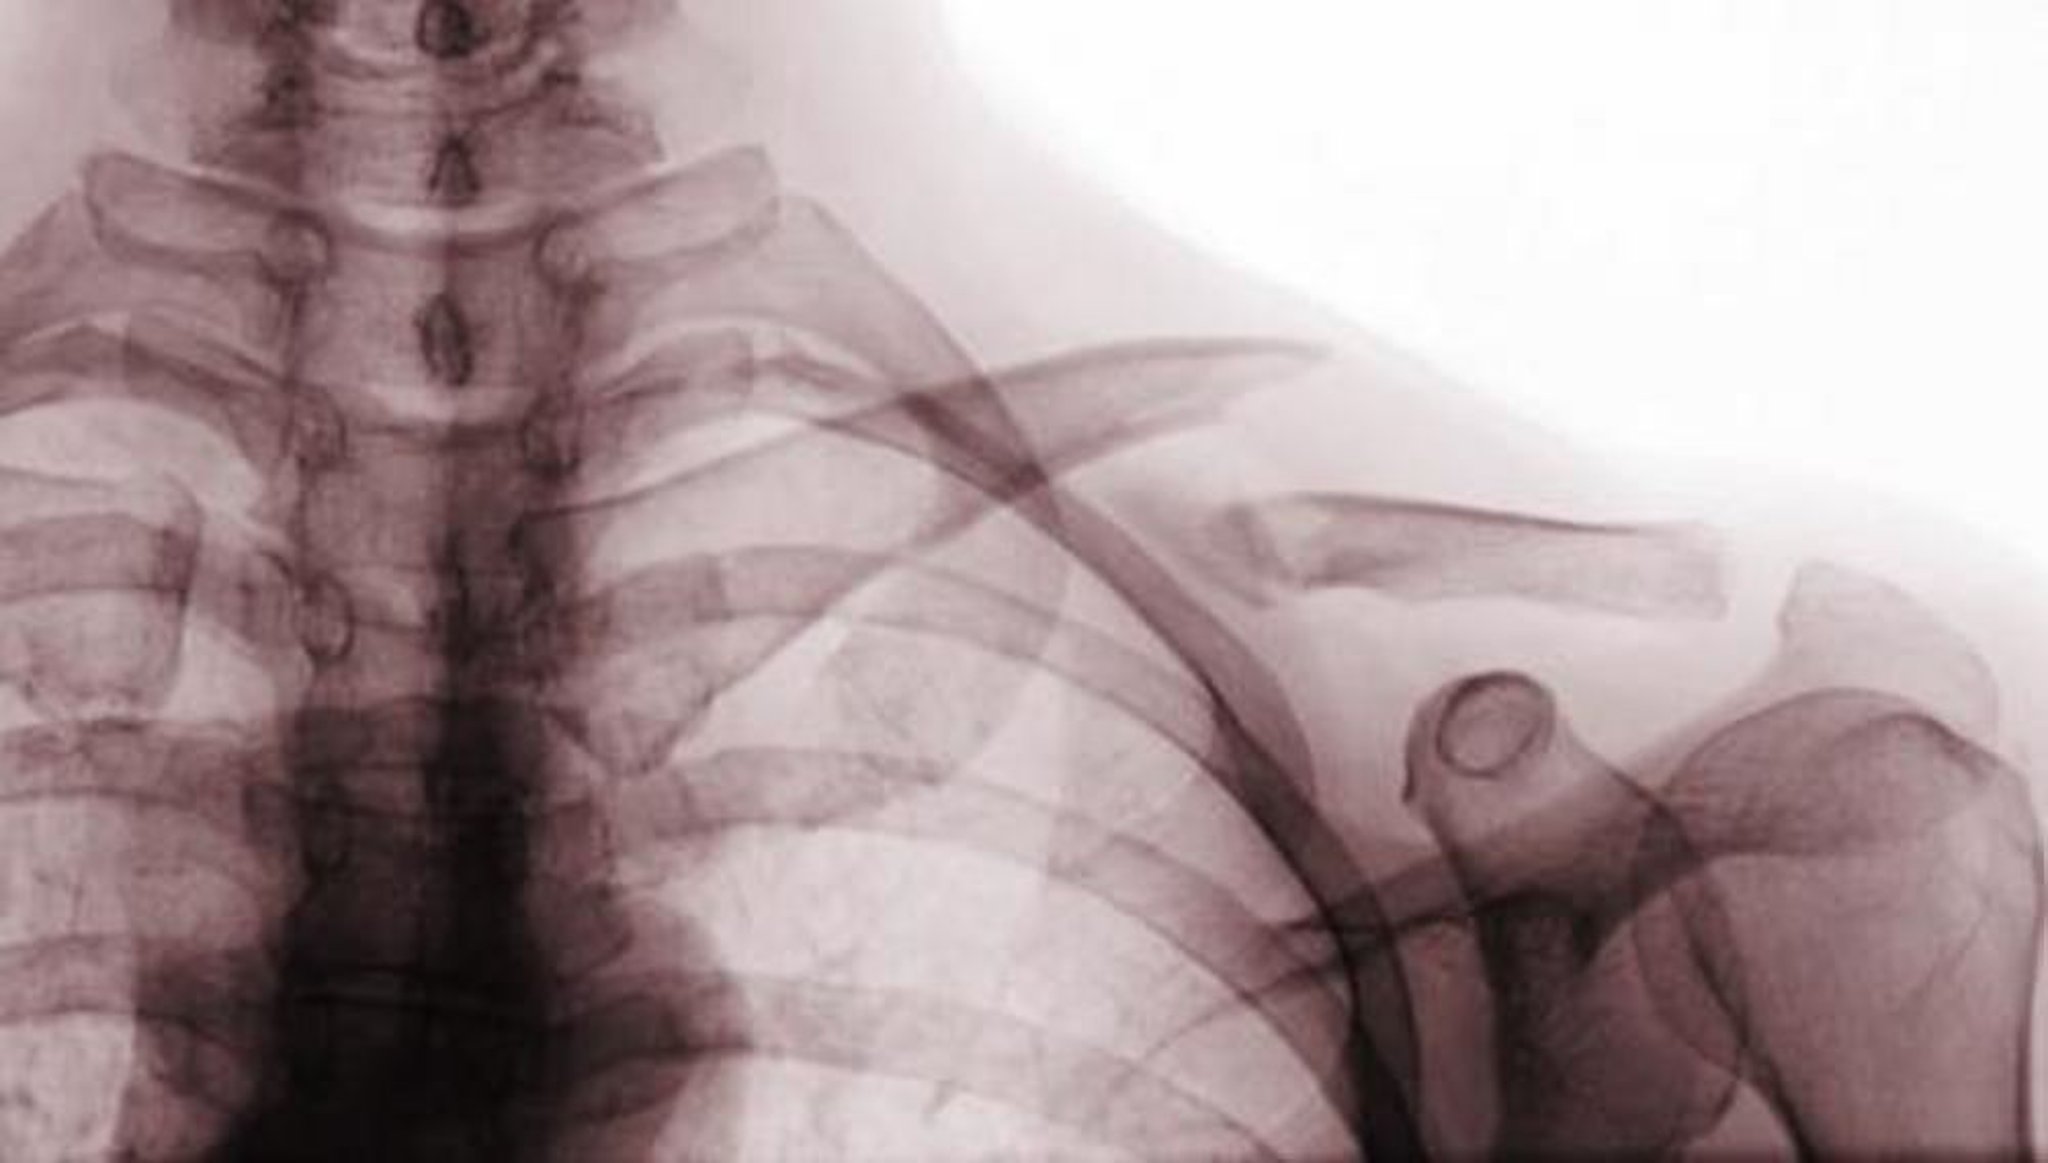

Fracture de la clavicule

Cette radiographie de face montre une fracture déplacée du tiers moyen de la clavicule (fracture de classe A).